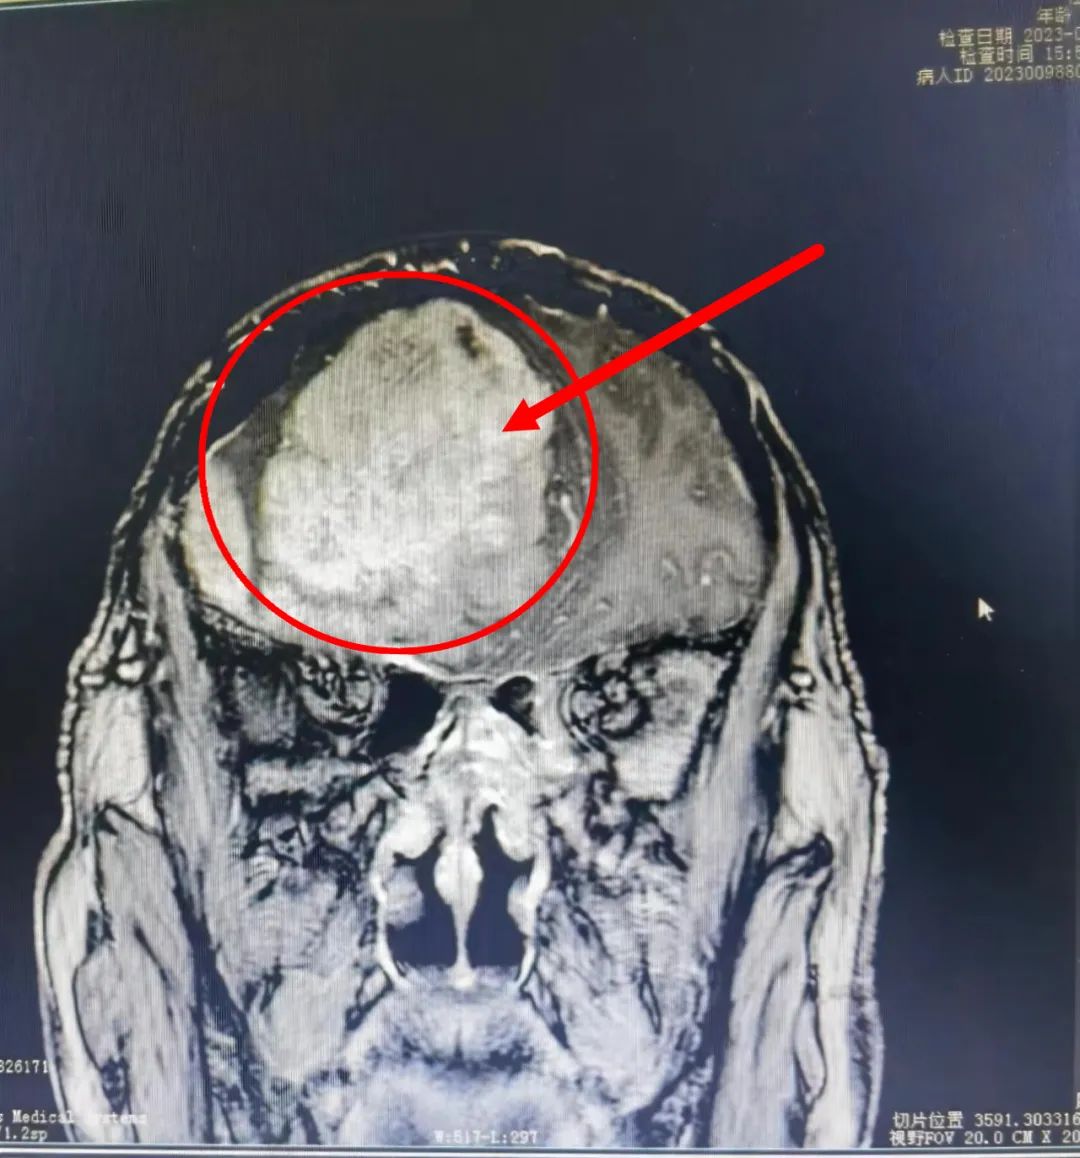

66岁的贺大爷(化名)平时下地干活特别麻利,也特别注重身体锻炼,自觉身体很棒,很少进行健康体检。七月中旬,贺大爷起床后发现眼睛视物不清,偶尔还有头痛、头昏的症状,家属见状立即将其送到绥宁县人民医院就诊检查。门诊CT检查提示右侧额部占位病变,考虑脑膜瘤可能性大,随即入住神经外科,并经中南大学湘雅医院驻绥专家廖新斌博士及县人民医院神经外科主任黄敏认真仔细讨论、会诊后,诊断为右侧巨大脑膜瘤,需进行手术切除。 当听到专家说是颅内肿瘤时,贺大爷顿时愣住了,家属也更加着急起来。廖新斌博士和黄敏主任立即安抚道:“脑膜瘤是颅内常见肿瘤,也是中枢神经系统最常见的原发性肿瘤,多为良性,生长缓慢且隐匿,手术切除肿瘤后均能取得很好的恢复效果,神经功能也能很快恢复。”并耐心为其说明手术治疗的优势和相关事项,对他们提出的各种疑问给予了细致的解答,最大程度地打消了贺大爷及家属对手术的顾虑,最终选择手术治疗。

术前VS术后

术前VS术后 在廖新斌博士和黄敏主任的带领下,神经外科团队认真讨论并充分做好术前准备,如期为贺大爷实施了“前颅窝底复发肿瘤”切除术。手术效果及术后恢复良好,贺大爷于8月3日康复出院,并对科室团队的专业技术和卓越服务竖起了大拇指,其家属也送来锦旗表示感谢。